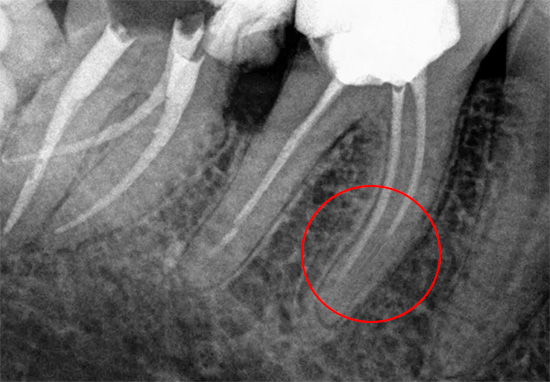

Material de enchimento removido no ápice da raiz do dente

Dentre todas as complicações que surgem após a limpeza e o preenchimento dos canais, a remoção do material de preenchimento fora da raiz é provavelmente um dos primeiros locais, apesar dos sistemas de controle dentário para a precisão desse procedimento. Quase todos os dentistas com experiência de mais de 10 anos, pelo menos uma centena de vezes, enfrentam essas situações quando, após remover o nervo e remover o material de preenchimento fora do ápice da raiz, o dente do paciente começa a doer severamente no dia do tratamento.

É possível diagnosticar tal complicação somente depois de estudar os dados de raios-X ou visográficos em um computador. Porém, a radiografia panorâmica de ambas as mandíbulas nem sempre permite um exame detalhado da parte superior das raízes dos dentes tratados e identifica o problema.

Se o comprimento do dente de trabalho for determinado incorretamente, não há ênfase apical, o pino de guta-percha não é dimensionado corretamente, o material é removido para a raiz do tecido circundante. Ao mesmo tempo, é possível observar no raio-x como a faixa branca do material de enchimento passa dentro da raiz, atinge seu ápice e continua. Mesmo uma pessoa que não é completamente avançada em odontologia pode diagnosticar facilmente o erro de um médico quando o alfinete de guta-percha se estende além da raiz em 4-5 milímetros ou mais.